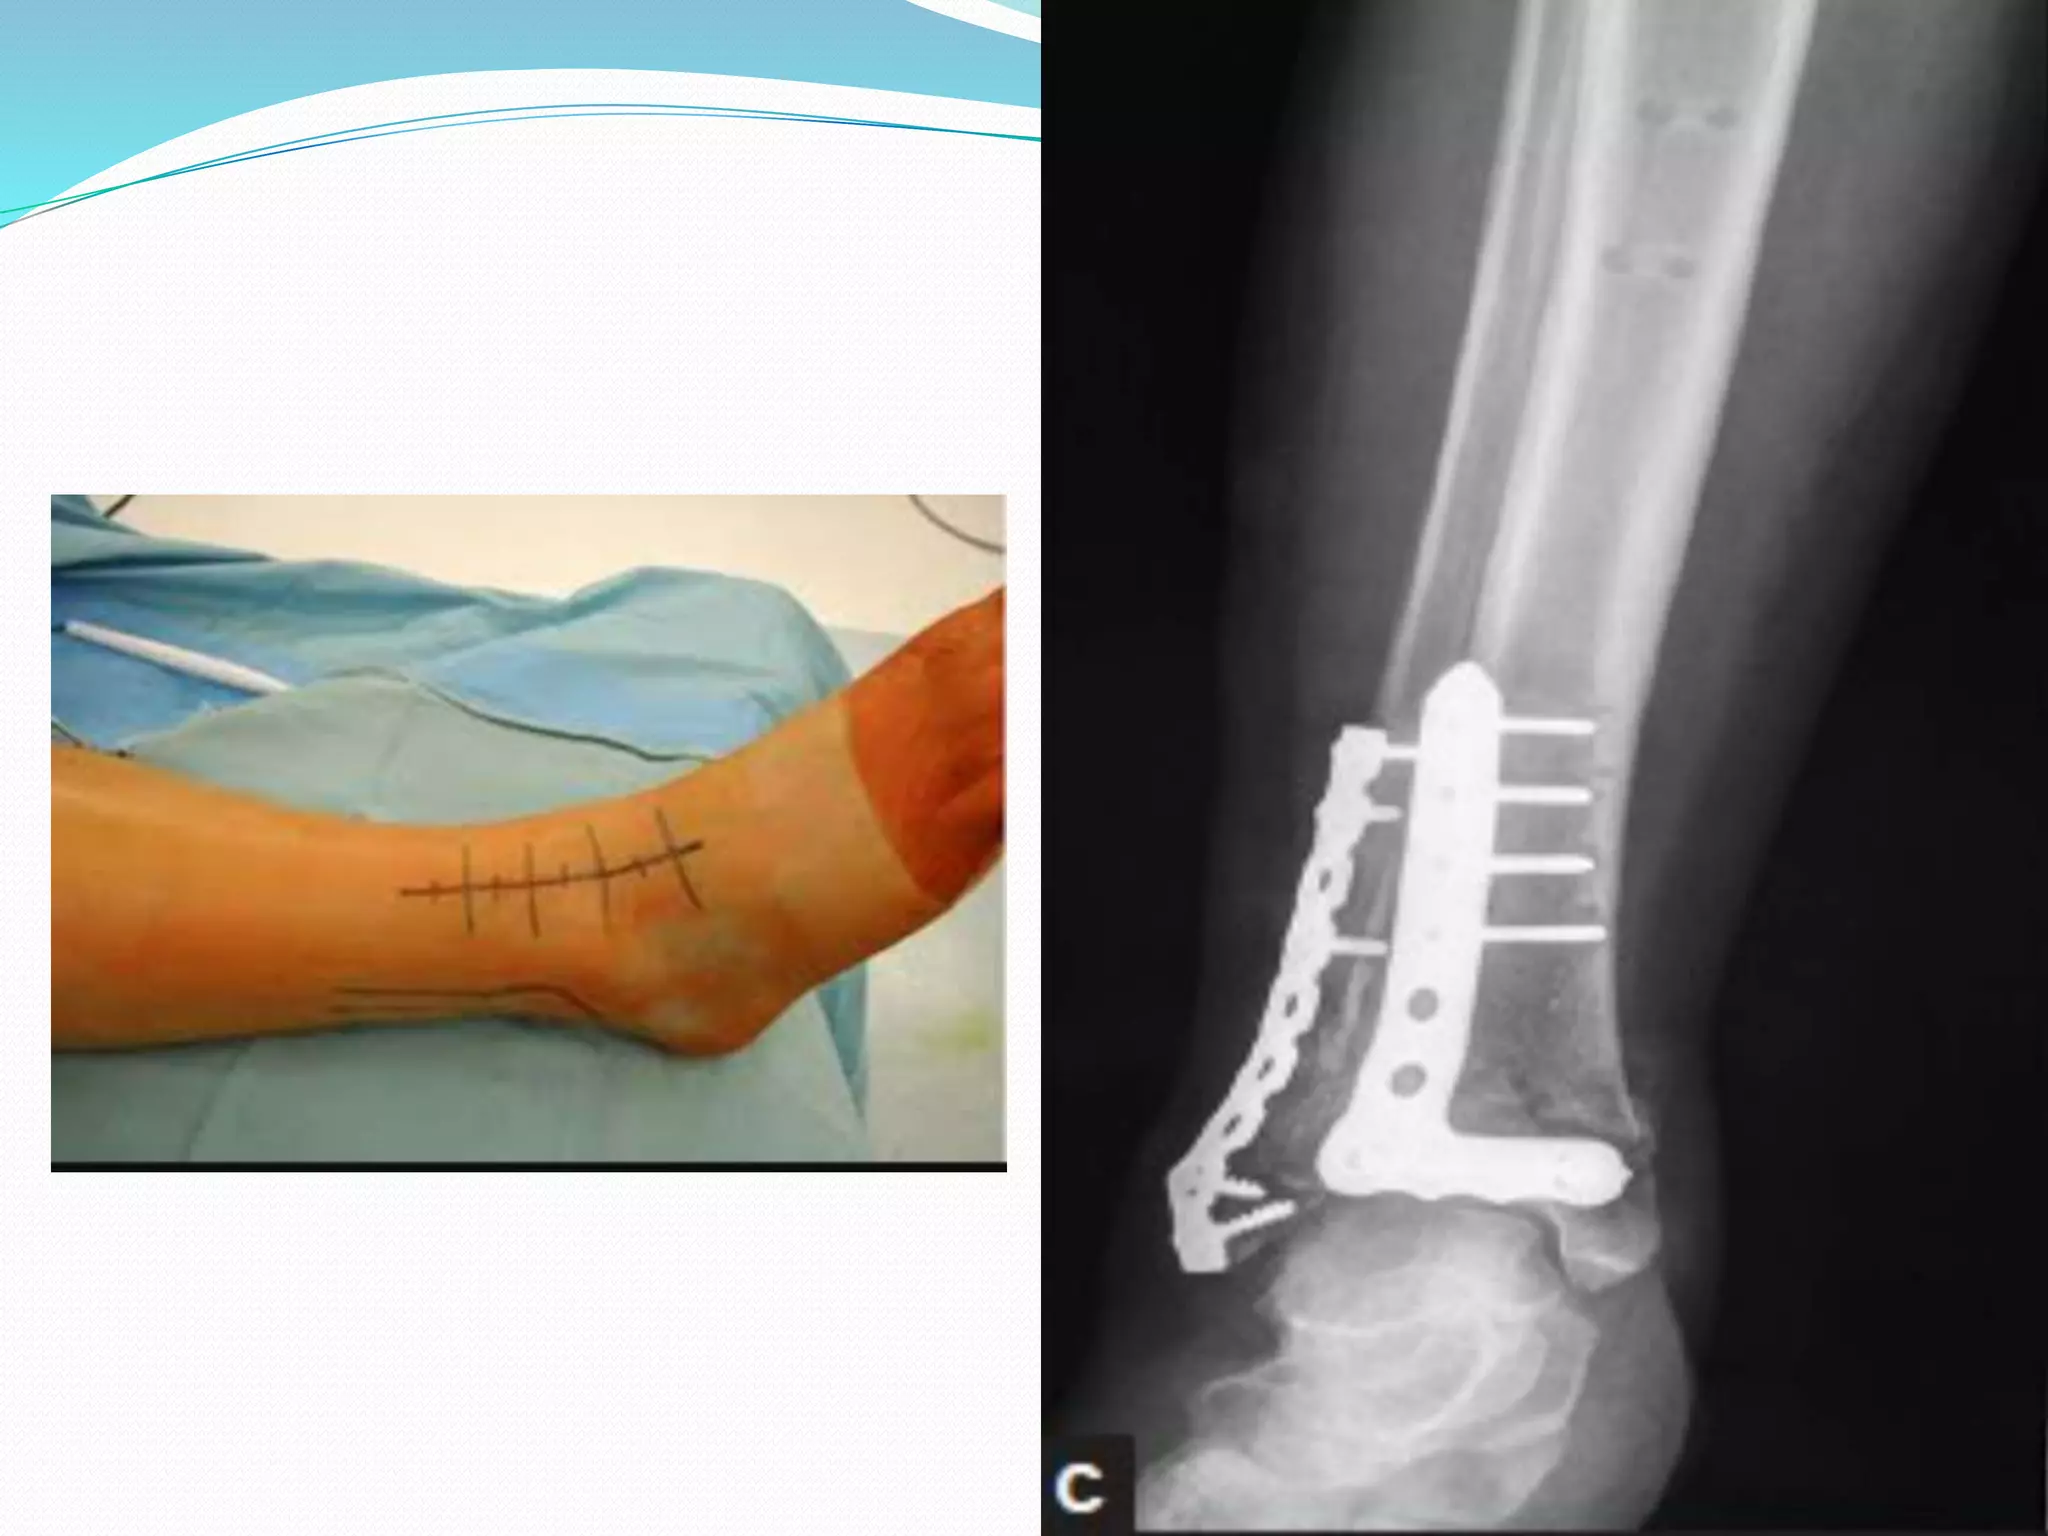

Second stage

 After 10-14 days average(10

days)

 Remove the Ex Fix

 Through antero lateral

incision

 Articular reduction & fixation

with pre countered plate and

screws

 Additional antero medial

incision may require to fix

MM or large medial fragment

 Two incision required-

maintain not<6-7 cm

between two incision